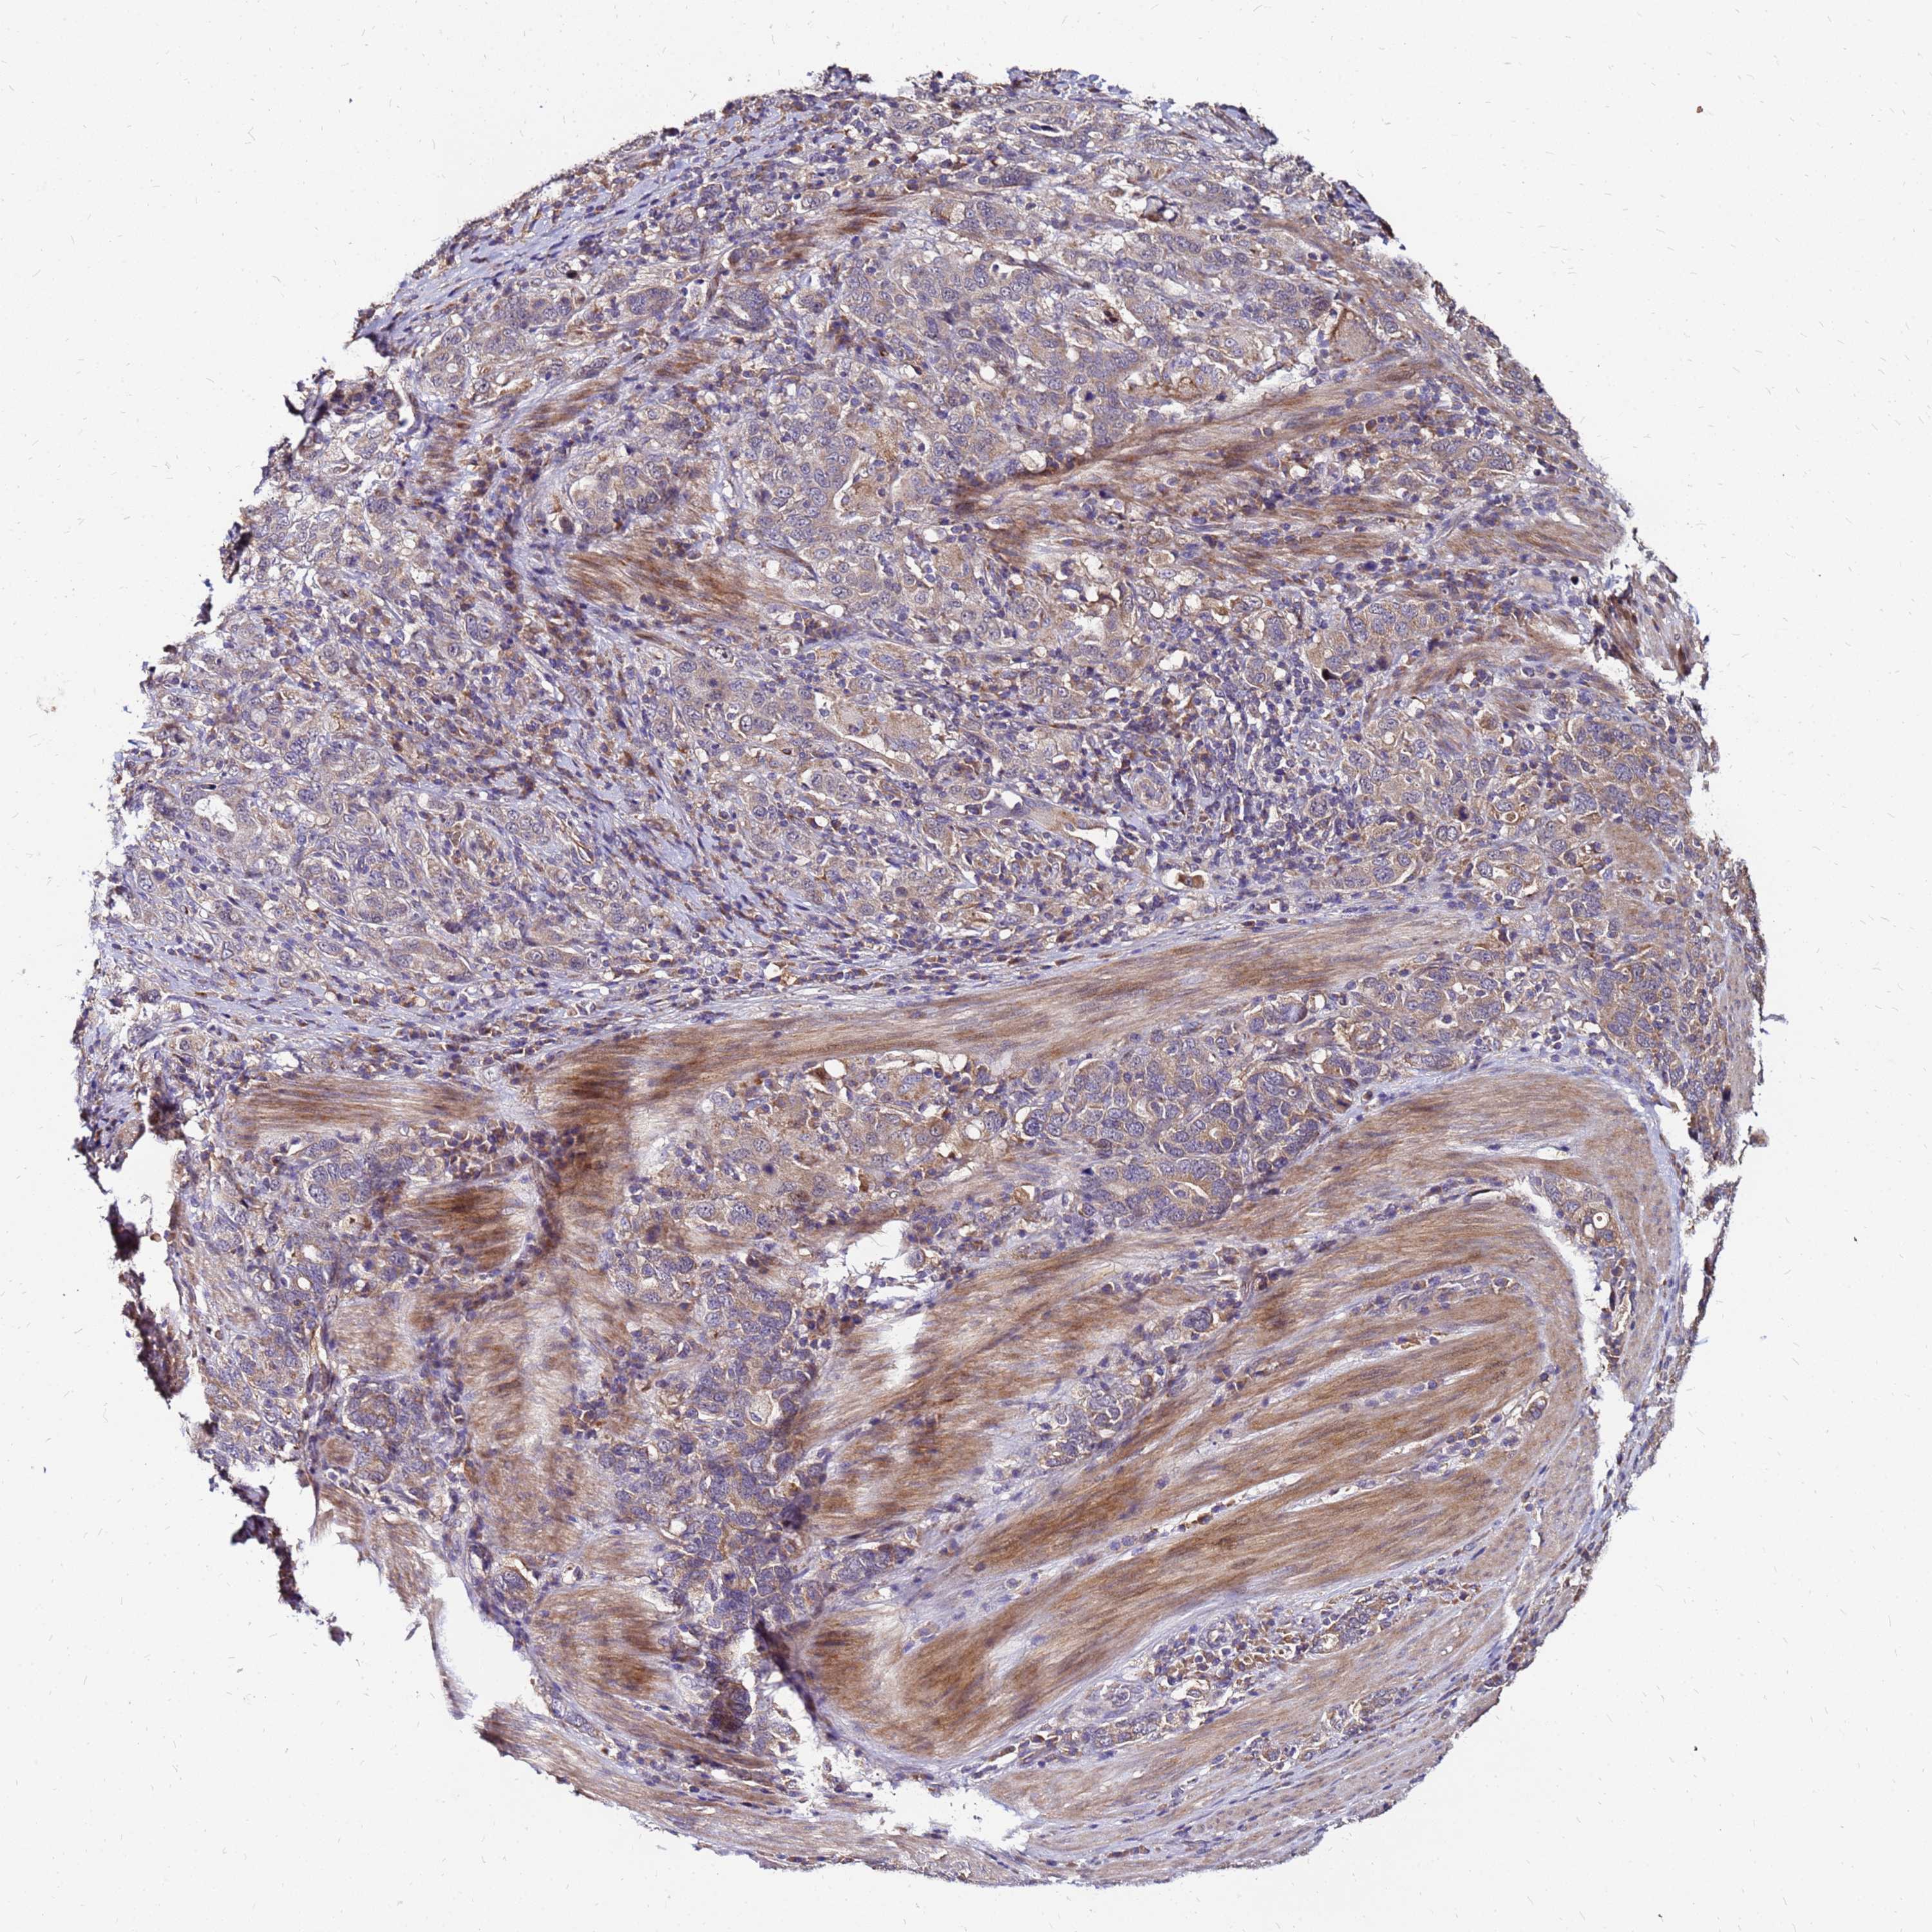

STOMACH CANCER - Protein expressioni

A mouse-over function shows sample information and annotation data. Click on an image to view it in a full screen mode. Samples can be filtered based on level of antibody staining by selecting one or several of the following categories: high, medium, low and not detected. The assay and annotation is described here.

Antibody stainingi

Antibody staining in the annotated cell types in the current human tissue is reported as not detected, low, medium, or high, based on conventional immunohistochemistry profiling in selected tissues. This score is based on the combination of the staining intensity and fraction of stained cells.

Each image is clickable and will lead to virtual microscopy that enables deeper exploration of all samples and also displays staining intensity scores, fraction scores and subcellular localization as well as patient and tissue information for each sample.

Antibody HPA044188

Antibody HPA045619

Antibody HPA045699

Staining

High

Medium

Low

Not detected

Intensity

Strong

Moderate

Weak

Negative

Quantity

>75%

75%-25%

<25%

None

Location

Nuclear

Cytoplasmic/membranous

Cytoplasmic/membranous,nuclear

Adenocarcinoma, NOS